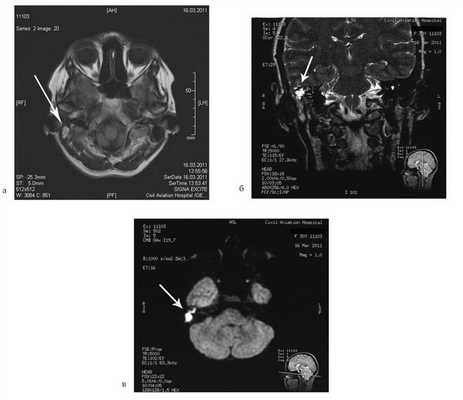

Больная У., 25 лет, обратилась с жалобами на снижение слуха на правое ухо, периодические выделения из правого уха. 18 лет назад была выполнена радикальная операция по поводу острого мастоидита, острого гнойного среднего отита справа. После операции развился парез лицевого нерва. В связи с продолжающимися обострениями через 8 лет была выполнена повторная операция с тимпанопластикой и мастоидопластикой. Частота обострений снизилась, но периодические выделения из уха продолжались. При отомикроскопии визуализируется неомембрана на задней стенке наружного слухового прохода с отверстием 2×4 мм, которое ведет в мастоидальную полость. Дно и стенки полости необозримы.

На КТ височных костей справа послеоперационная полость, заполненная мягкотканным образованием, определяется большой костный дефект в направлении сигмовидного синуса и мозжечка (рис. 2, а). Рисунок 2. КТ и МРТ височных костей больной У. с хроническим правосторонним средним отитом. Состояние после радикальной операции (1993 г.), санирующей операции с мастоидопластикой и тимпанопластикой (2003 г.). Холестеатома. Парез лицевого нерва. а — КТ; б — МРТ основания черепа в режиме Т1; в — в режиме Т2; г — в режиме non-EPI DWI.

Больной была выполнена МРТ (рис. 2, б—г).

В режимах Т2 и non-EPI DWI определяется сигнал высокой интенсивности, в режиме Т1 — низкоинтенсивный сигнал. Это может свидетельствовать о наличии холестеатомы мастоидальной полости и пирамиды височной кости. Диагноз: хронический правосторонний средний отит; состояние после радикальной операции в 1993 г. и санирующей операции с мастоидопластикой и тимпанопластикой в 2003 г.; холестеатома; парез лицевого нерва.

Больной произведена санирующая реоперация, в ходе которой удалена холестеатома больших размеров, заполняющая отшнурованную послеоперационную полость. Эта полость распространялась до верхушки сосцевидного отростка, граничила с твердой мозговой оболочкой и достигала верхушки пирамиды височной кости. Полость облитерирована. В послеоперационном периоде получен хороший функциональный результат. Ухо толерантно к воде, не было обострений, гноетечения, головокружений. Сохранилась кондуктивная тугоухость I степени. МРТ через 9 мес подтвердила отсутствие холестеатомы.